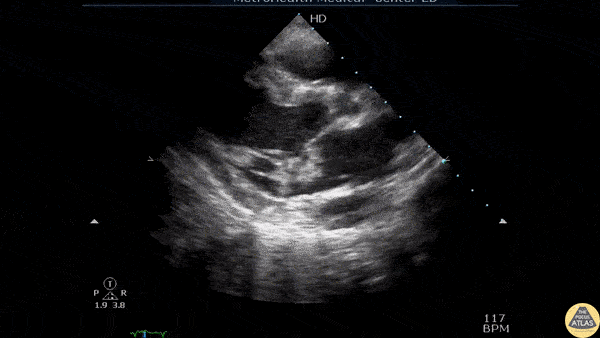

A patient presented to the ED with fever, sepsis, Janeway lesions, Osler nodes, and splinter hemorrhages. PLAX view revealed a vegetation on the mitral valve indicative of MV endocarditis. Image courtesy of Robert Jones DO, FACEP @RJonesSonoEM Director, Emergency Ultrasound; MetroHealth Medical Center; Professor, Case Western Reserve Medical School, Cleveland, OH View his original post here